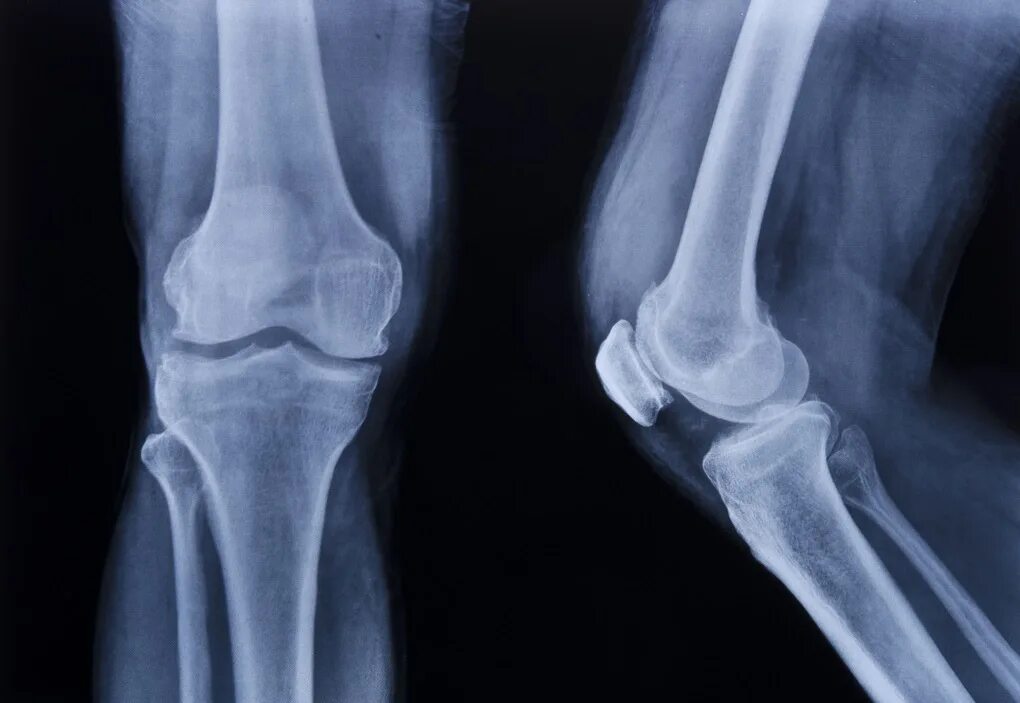

Рентгенография коленного сустава 2 проекции